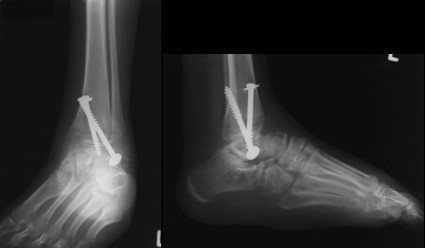

Die Patientin konsultierte erneut Ärzte, um eine Behandlung durchführen zu lassen. Es zeigte sich radiologisch eine Arthrose im Bereich des unteren Sprunggelenkes. Schliesslich wurde ihr angeraten, das untere Sprunggelenk aufgrund der schmerzhaften Arthrose versteifen und einzeitig die Versteifung des oberen Sprunggelenkes rückgängig machen zu lassen und ein Kunstgelenk implantieren zu lassen, um eine komplette Steifigkeit des Rückfusses zu vermeiden. Die Patientin willigte ein und liess die Operation im Februar 2002 durchführen.

Im Jahr 2006 stellt sich die Patientin in der Fusschirurgie der Schulthess Klinik vor. Die Untersuchung zeigte ein hinkendes Gangbild mit Entlastung des linken Fusses. Der Fuss selbst zeigte eine Fehlstellung als Residuum der angeborenen Klumpfussdeformität. Das Bewegungsausmass im Bereich des oberen Sprunggelenkes betrug 5° nach oben und 10° nach unten. Das gesamte Gelenk stellte sich überwärmt und druckschmerzhaft dar. Die im Rahmen der Konsultation durchgeführten Röntgenaufnahmen zeigten, dass die untere Prothesenkomponente, welche im Bereich des Sprungbeines verankert ist, nach unten eingesunken war. Die Schraube, die diese Komponente fixiert war gebrochen. Es bestand der Verdacht einer Nekrose (=abgestorbener Knochen) im Bereich des Sprungbeines.